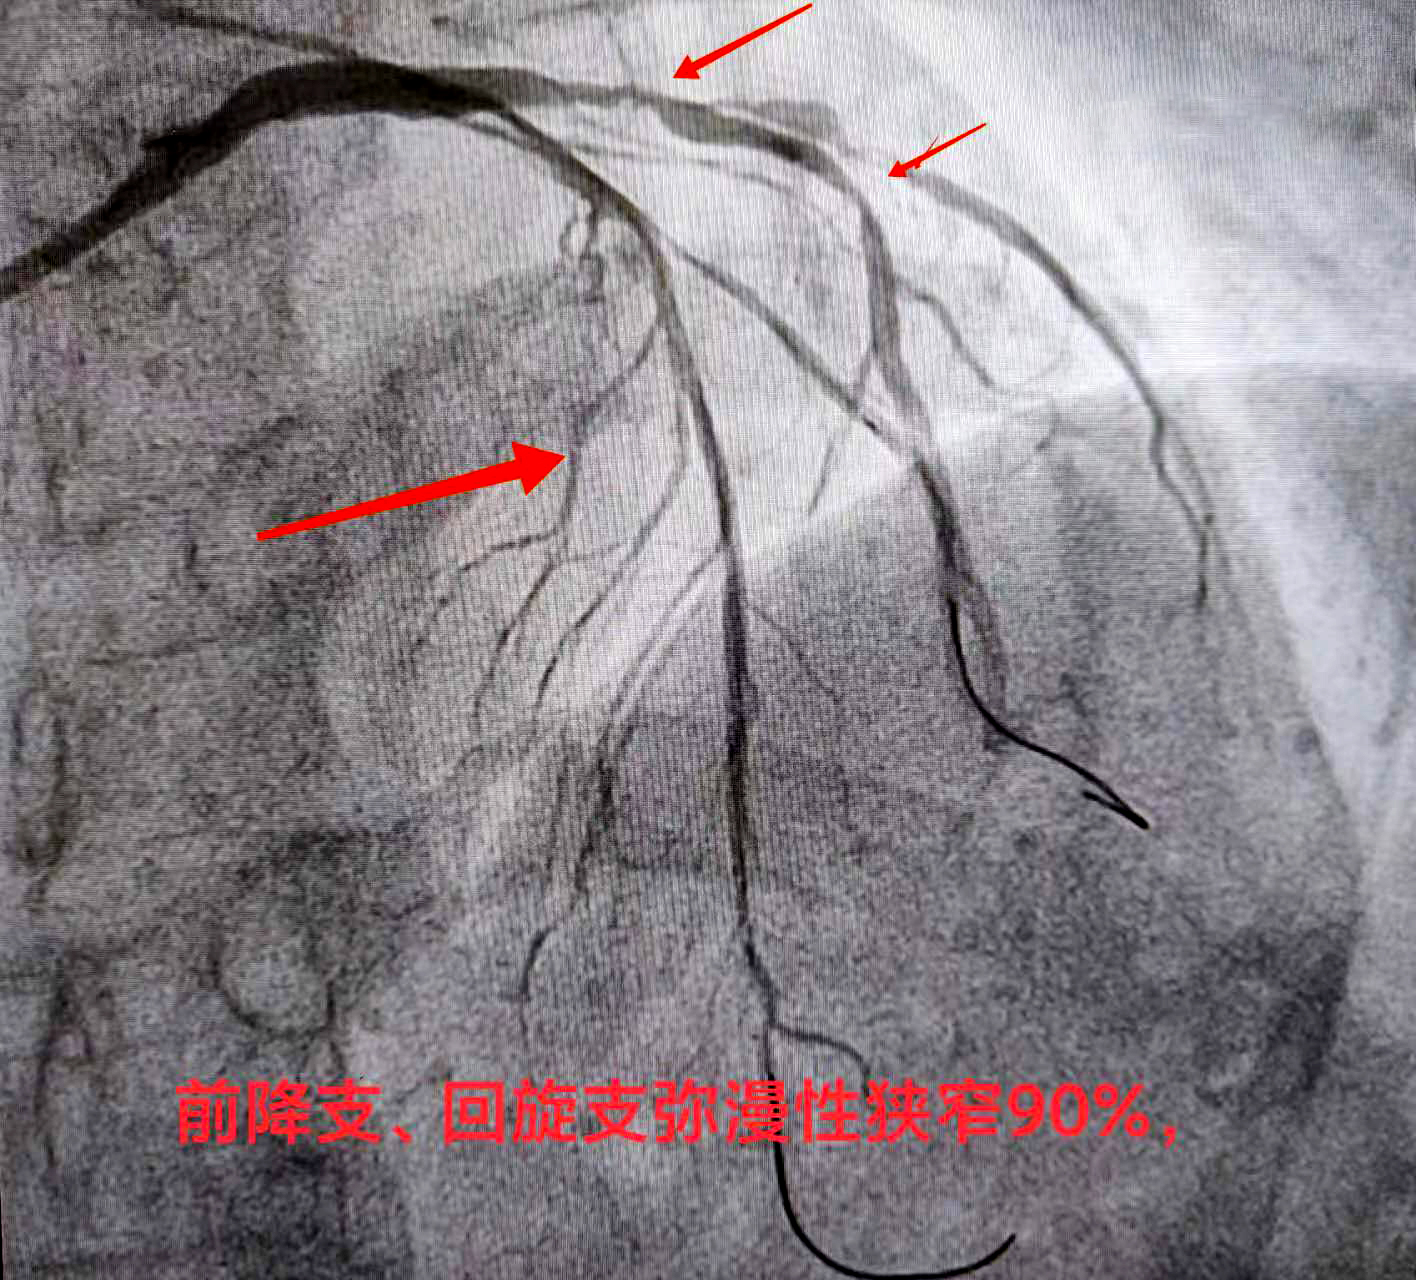

熊斌主任在接诊后立即为赵某做相关检查,结果显示严重三支病变——即为心脏供血的三条大血管前降支血管、回旋支血管、右冠状动脉,甚至包括左主干都存在狭窄病变,狭窄程度达90%以上,属于弥漫性狭窄病变。通俗地讲,就是赵某的冠脉血管近乎全都堵塞不通,血液无法顺畅供给心脏,这导致了心脏缺血,从而引起胸闷、胸痛、心慌气短等不适症状,严重者还会导致心肌坏死、心梗发生,严重威胁生命健康。